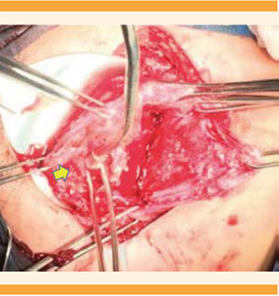

Dos semanas posteriores a la recuperación de la alteración respiratoria y hemodinámica la paciente tuvo actividad uterina y ruptura prematura de membranas: se programó la finalización del embarazo mediante cesárea e histerectomía obstétrica, por acretismo placentario focal a nivel de la pared anterior a 2 cm del cuello uterino. El recién nacido, masculino, de 34 semanas de gestación por Capurro, con peso de 2590 gramos, Apgar 7/8 Silverman Anderson de 2. El sangrado se estimó en 1200 mililitros. (Figura 6) La paciente evolucionó satisfactoriamente y fue dada de alta del hospital sin contratiempos.